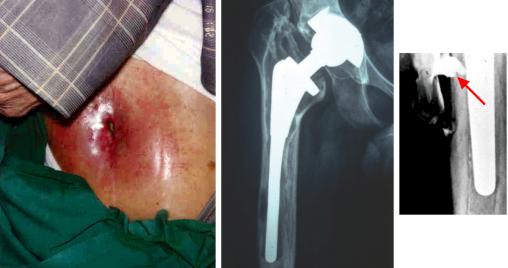

Infection sur prothèse de hanche descellée infectée et fistulisation cutanée chronique